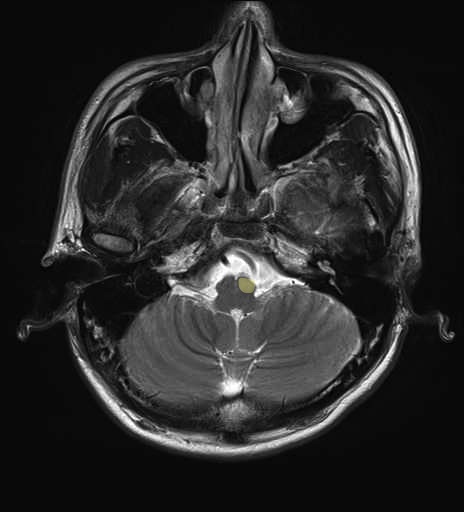

運動系 錐体路系に色を付けました。

■皮質脊髄路(いわゆる錐体路):一次運動野から脊髄遠隔の下位運動ニューロン細胞体まで